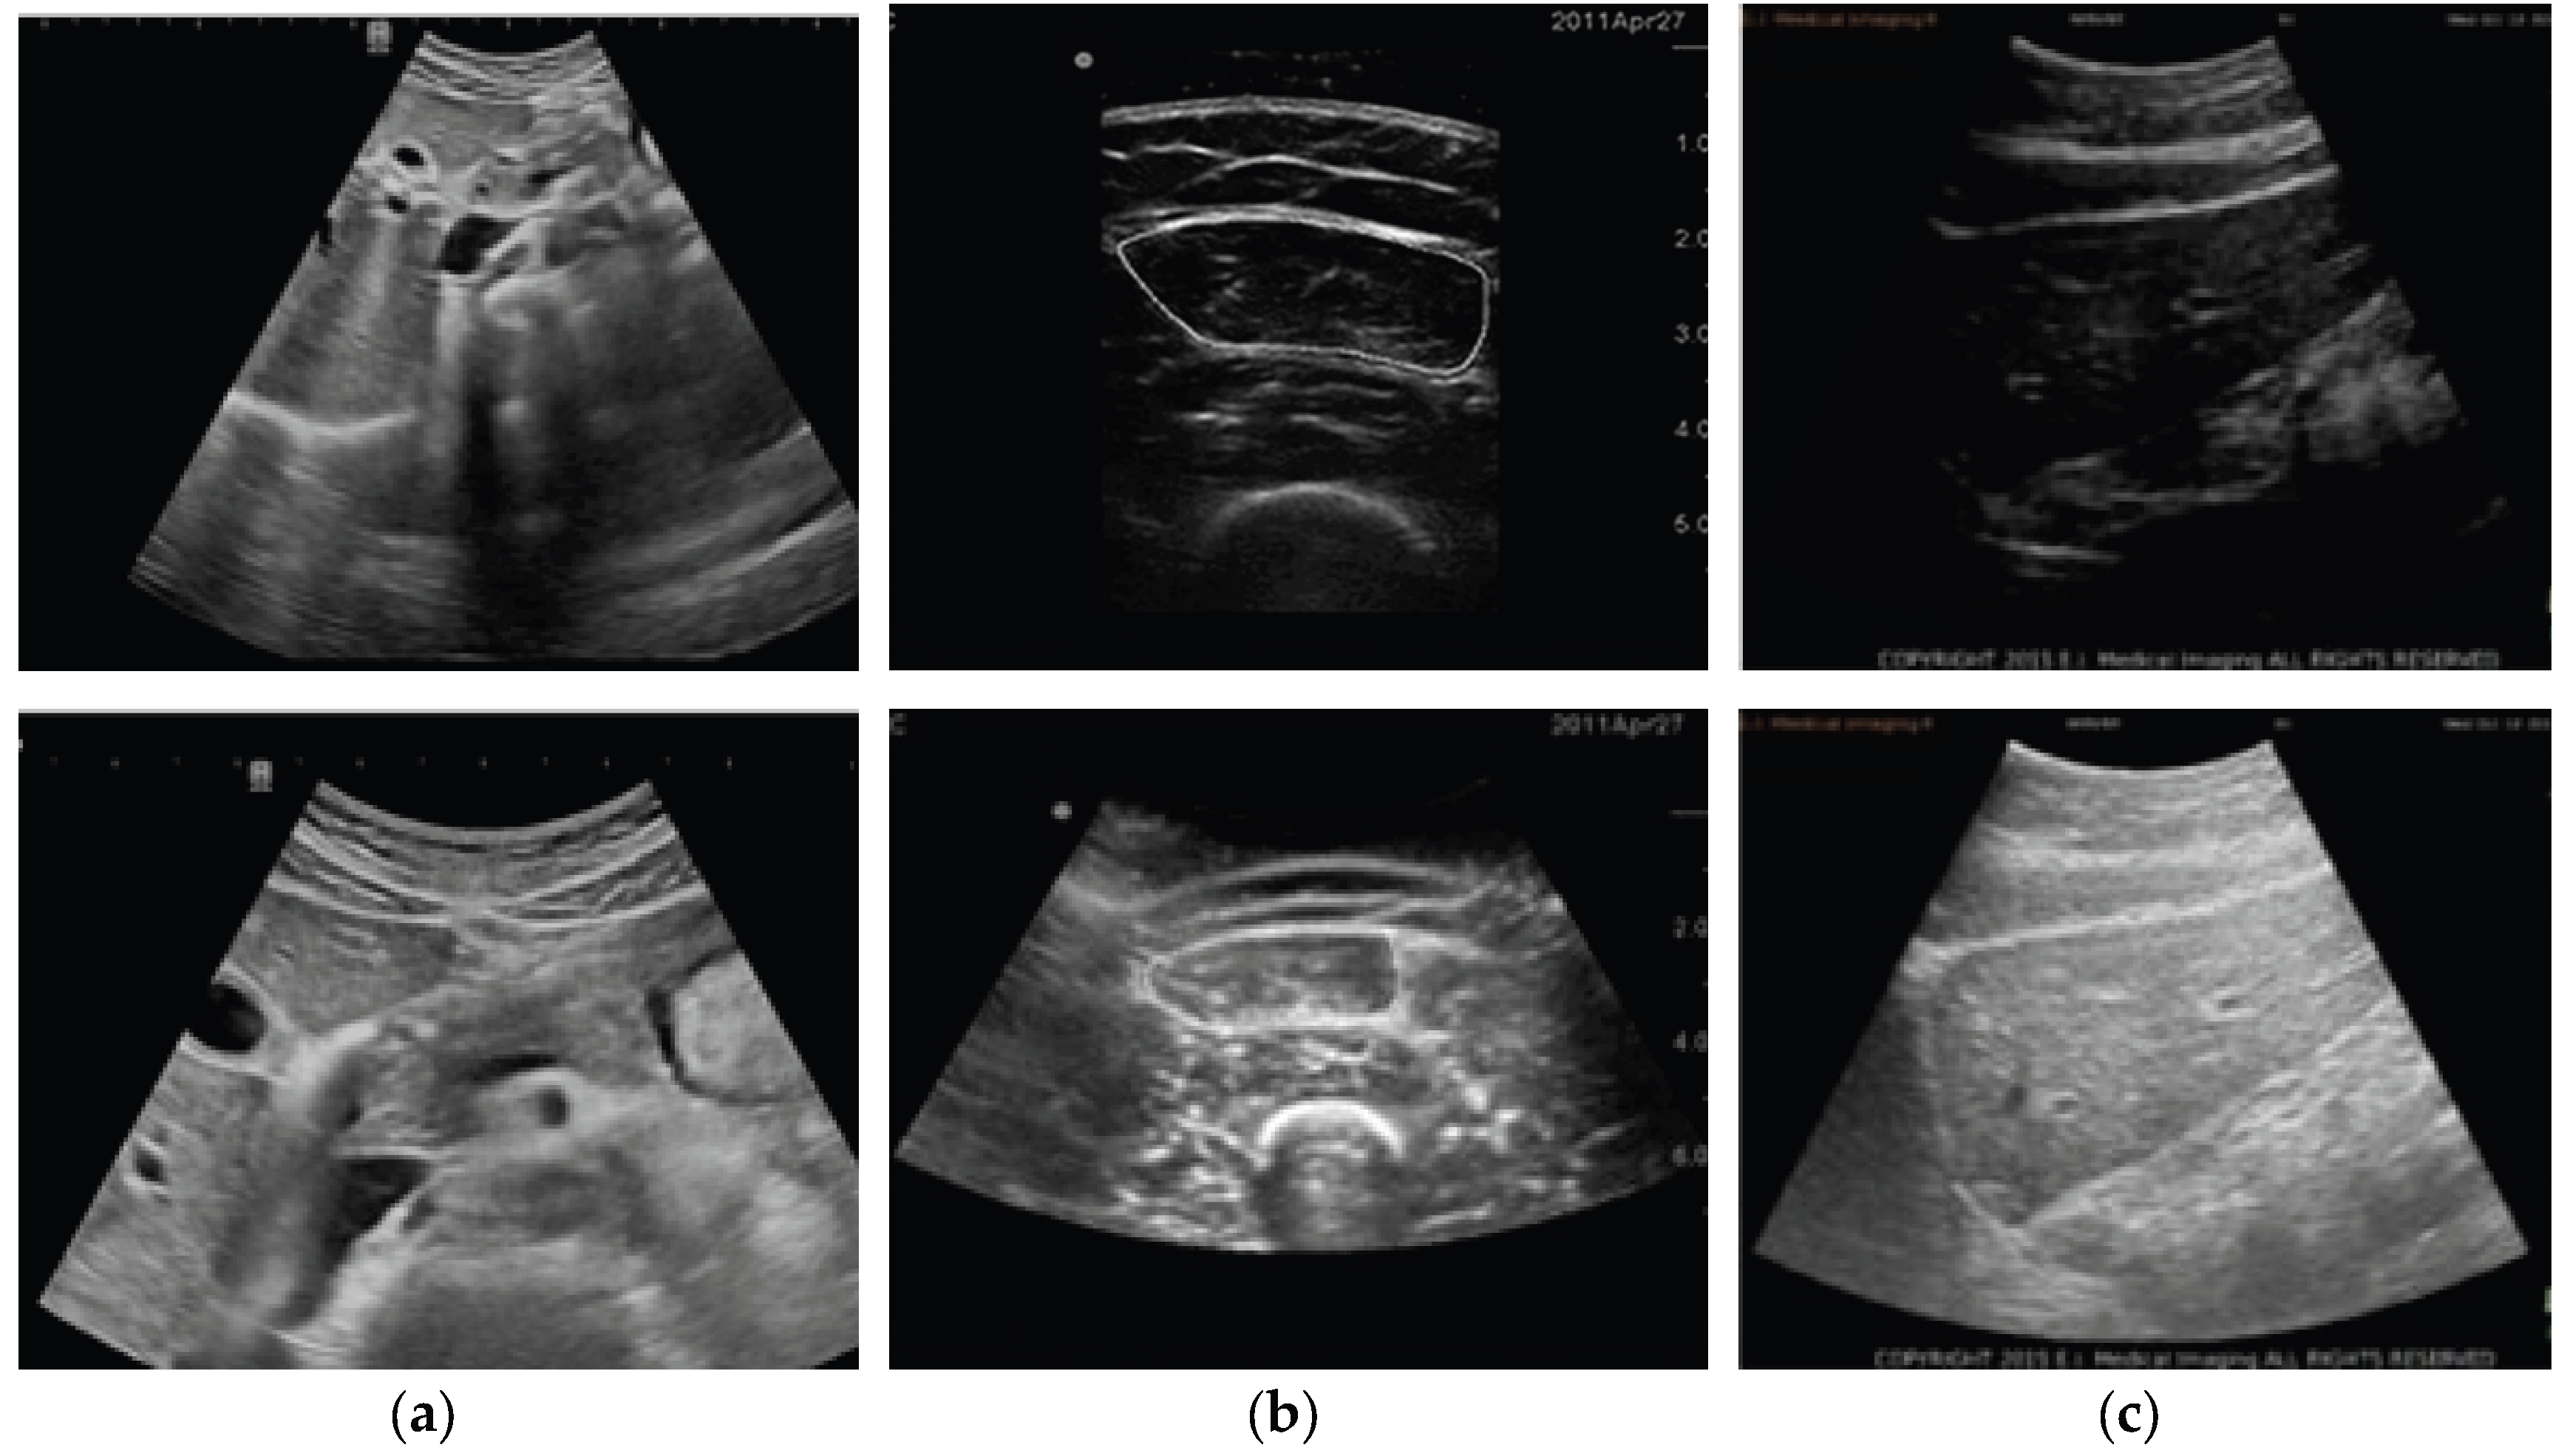

- Anatomy (Breast/ Fetal/ Cardiac/ Abdominal/Musculoskeletal/Others);